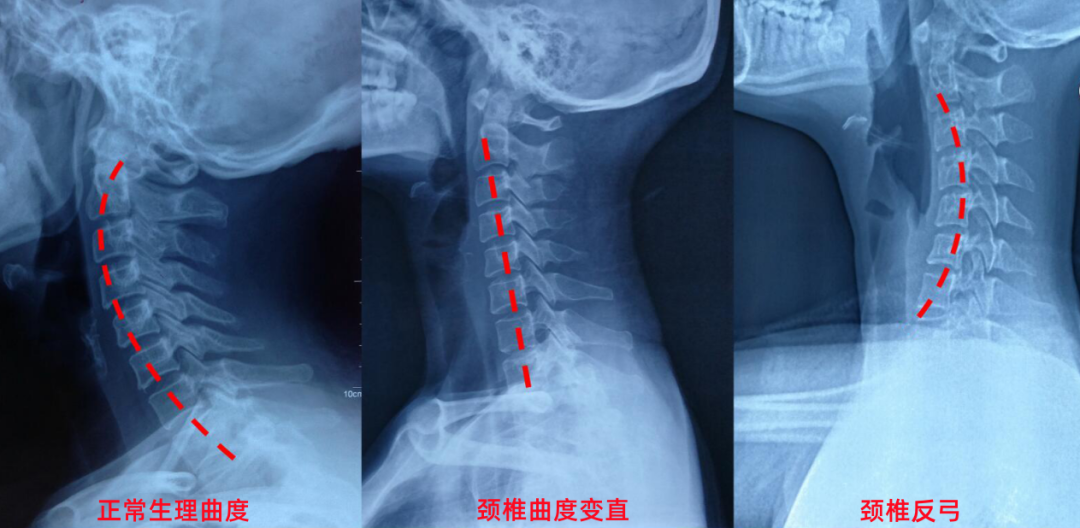

从客观角度讲,外观上没有明显变化,可能有部分人会有明显的头前引、肩部内扣等。而在放射诊断中,尤其是X光检查,往往会发现颈椎曲度变直,甚至出现反弓现象,正常情况下颈椎是有向前弯曲的生理曲度。